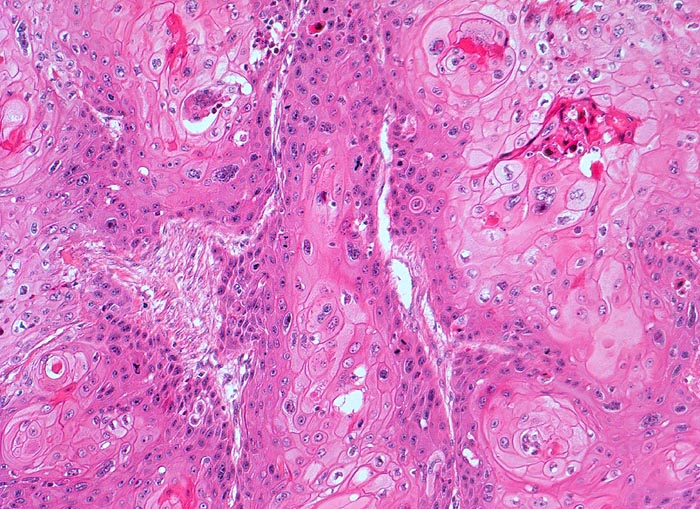

n/ Plattenepithelkarzinom der Harnblase

Plattenepithelkarzinom der Harnblase

Der zytologische Befund entspricht dem der Plattenepithelkarzinome an anderen Orten. Allerdings finden sich oft auffallend wenig Tumorzellen, die überdies oft nur geringe Atypien aufweisen.